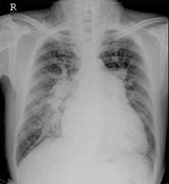

醫(yī)學影像學的發(fā)展經(jīng)歷了三個階段:X線的臨床應用,放射學的形成,醫(yī)學影像學的形成。

總體走向是建立現(xiàn)代醫(yī)學影像學:從大體形態(tài)學向分子、生理、功能代謝基因成像過渡;從膠片采集、顯示向數(shù)字采集電子傳輸發(fā)展;對比劑從一般性組織增強向組織疾病特異性增強發(fā)展;介入治療,以及與內(nèi)鏡、微創(chuàng)治療外科的融合、發(fā)展。

具體走向是:影像信息更加具有敏感性、直觀性、特異性、早期性;圖像分析由定性向定量發(fā)展:由顯示診斷信息向提供手術路徑方案發(fā)展;圖像采集與顯示:由二維模擬向三維全數(shù)字化發(fā)展;圖像存儲由膠片硬拷貝向軟拷貝無膠片化,乃至圖像傳輸網(wǎng)絡化發(fā)展;從單一圖像技術向綜合圖像技術發(fā)展。

從醫(yī)學影像學的角度講,其未來發(fā)展將集中四個特點:①醫(yī)學影像技術的數(shù)字化;②醫(yī)學影像技術的網(wǎng)絡化;③醫(yī)學影像技術的融合化;④醫(yī)學影像技術的標準化。